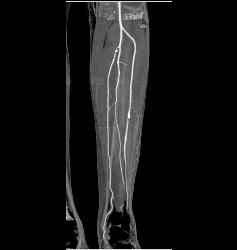

Popliteal Artery With Disease in Trifurcation Vessels- See Full Sequence